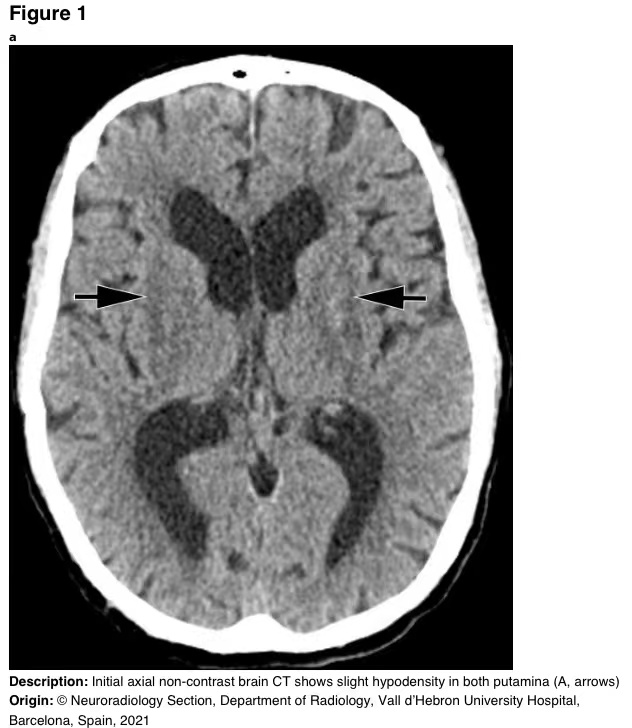

实验室检测显示,血液pH值为6.9,阴离子间隙高,乳酸水平为5mmol/L,血清甲醇浓度为190mg/dL。入院时脑部CT平扫显示,两个壳核均出现离散性低密度(图1)。静脉注射碳酸氢钠以纠正严重的酸中毒,然后注射乙醇和血液透析。

图1 脑CT平扫显示两个壳核轻度低密度(A,箭头)